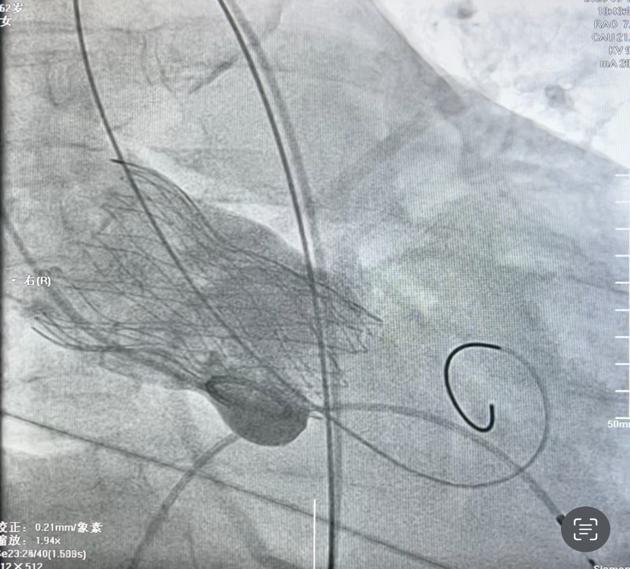

患者之一为63岁女性,胸闷胸痛不适一年多,近段时间反复出现胸闷胸痛不适,来院就诊检查为“冠心病、心绞痛、高血压病3级、2型糖尿病”收治入院。心脏超声提示左房增大,室间隔增厚,升主动脉略增宽,瓣膜重度反流。术前冠脉造影未见明显异常。主动脉瓣重度返流患者药物治疗效果不明显,需手术干预。经术前CTA评估,梁有峰主任及我院多学科充分术前讨论,制定了详细手术方案。在梁有峰主任指导下,心血管内科一病区医疗团队成功为该患者植入 TaurusElite AV29瓣膜,术后超声结果显示瓣膜工作正常,血流动力学良好,术后第二天即由ICU病房转入普通病房。

病例1:重度主动脉瓣关闭不全瓣膜植入 病例2:重度主动脉瓣狭窄瓣膜植入